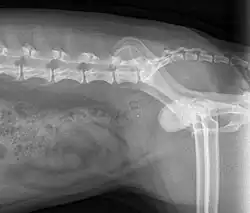

| X-Ray | |